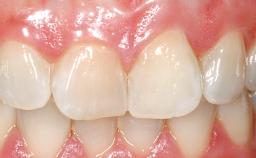

Immediate Placement of an Implant in a Maxillary Right Central Incisor Site

A 30-year-old female patient was referred to the office for the treatment of tooth 11. Her chief concern at the initial visit was to inquire, “Why is my tooth pink?” Upon clinical examination, it was determined that tooth 11 had a previous history of trauma and that the clinical crown had become noticeably pink in color as a result of internal resorption. This diagnosis was confirmed radiographically, indicating a large radiolucency involving the central and distal portions of the clinical crown. It was determined that restoration of this tooth was not possible, and that extraction was indicated. The presence of a mid-line diastema, which the patient wanted to reproduce, directed the treatment plan for tooth replacement utilizing a dental implant.

| Mesio-Distal Space | Asymmetry greater than 1 mm |